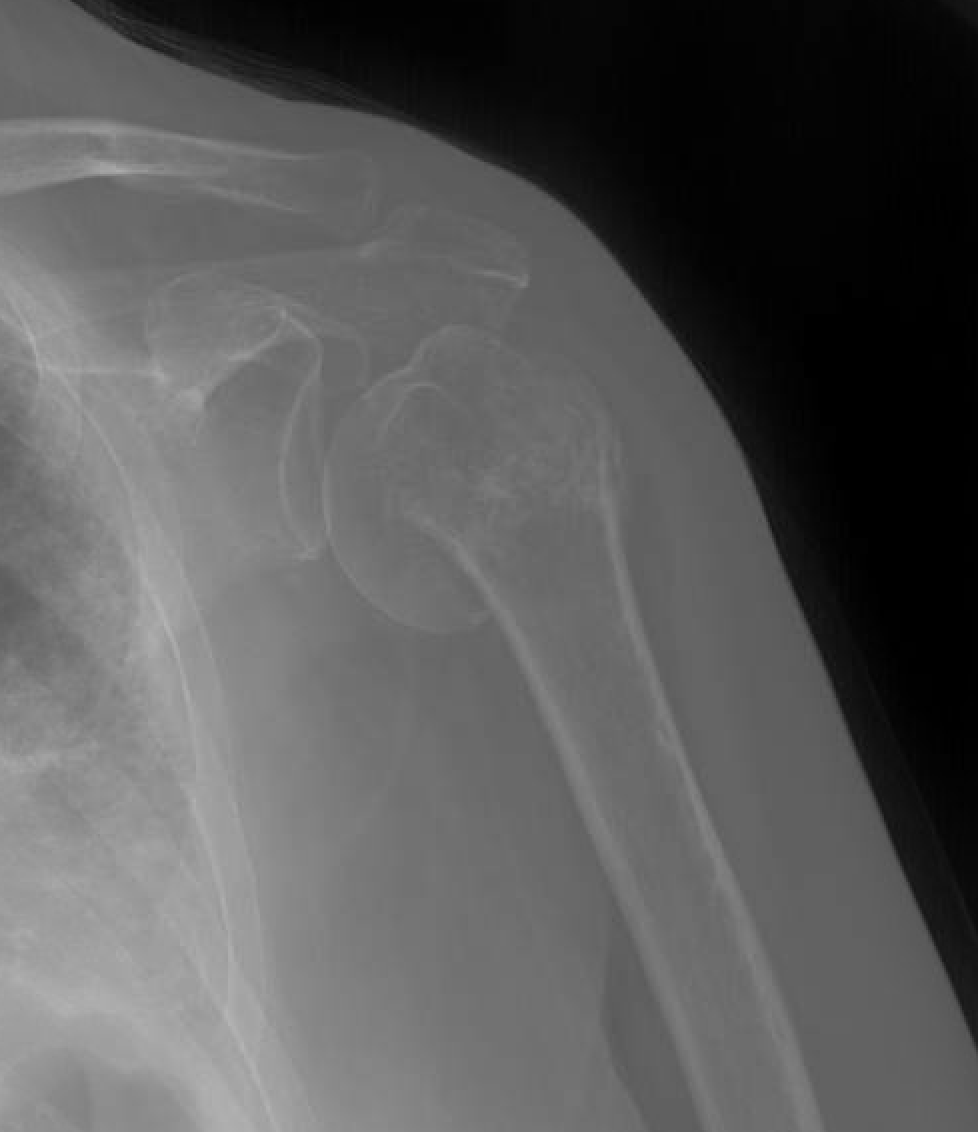

a Postoperative Grashey view of right shoulder showing expected changes Shoulder Subluxation No Pain in some people, a partial dislocation of the shoulder is not actually painful. It is more annoying, preventing. a shoulder subluxation is a partial shoulder dislocation involving the ball of the upper arm bone (the humerus). Describe the diagnostic approach for evaluating shoulder subluxation injuries. shoulder subluxation happens when the ball of the upper arm bone comes. Shoulder Subluxation No Pain.

Shoulder dislocation anterior Image Shoulder Subluxation No Pain a shoulder subluxation is a partial shoulder dislocation involving the ball of the upper arm bone (the humerus). In this condition the humeral head slips out of the glenoid cavity as a result of weakness of rotator cuff or looseness of the glenohumeral ligaments. What is shoulder subluxation and how is it treated? Describe the diagnostic approach for evaluating. Shoulder Subluxation No Pain.